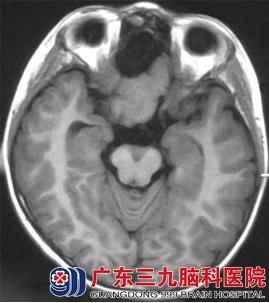

CT表现(图1、2):前颅窝底可见一等密度(与脑实质密度相同)占位性病变,其前方可见囊性的低密度影,与脑脊液密度相似,相邻脑组织受推压,未见明显水肿密度影。MR表现(图3-6):病变呈等T1等T2信号,边界清晰;其前方可见长T1长T2信号影,增强后,病变未见强化。弥散加权成像(DWI):未见病变弥散受限,前方囊性部分呈低信号。考虑为前颅窝脑外占位性病变。

图3 T1WI轴位:前颅窝底见等信号的团块状占位,其前方见囊性脑脊液低信号影